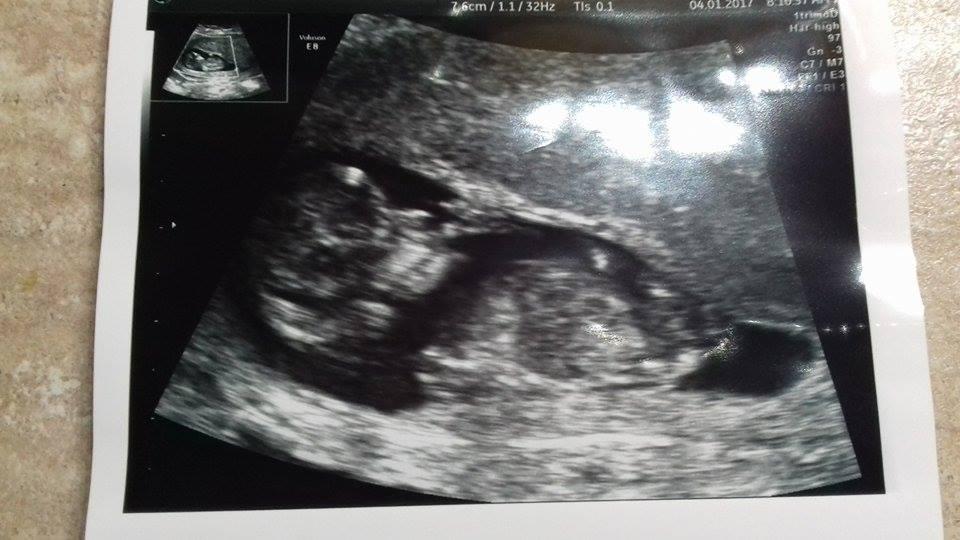

tak ako som slubila pridavam fotku mojho drobceka 🙂